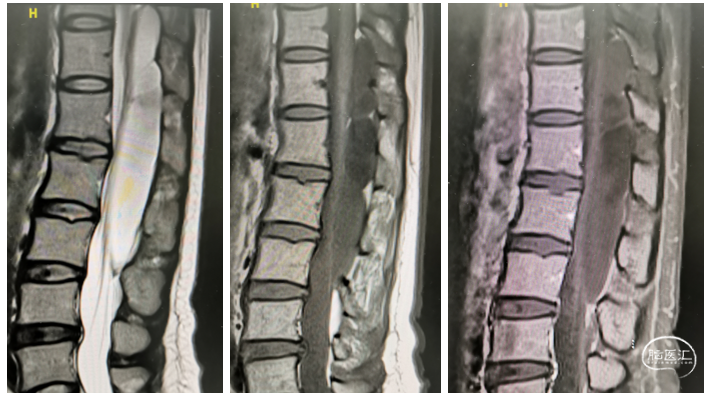

术前胸腰椎CT及MR如下:

图1 胸腰椎CT及MR检查提示:T11-L3椎管内硬膜下异常信号灶,考虑良性,脊髓硬膜内脊膜囊肿?神经鞘瘤?相应脊髓受压等。